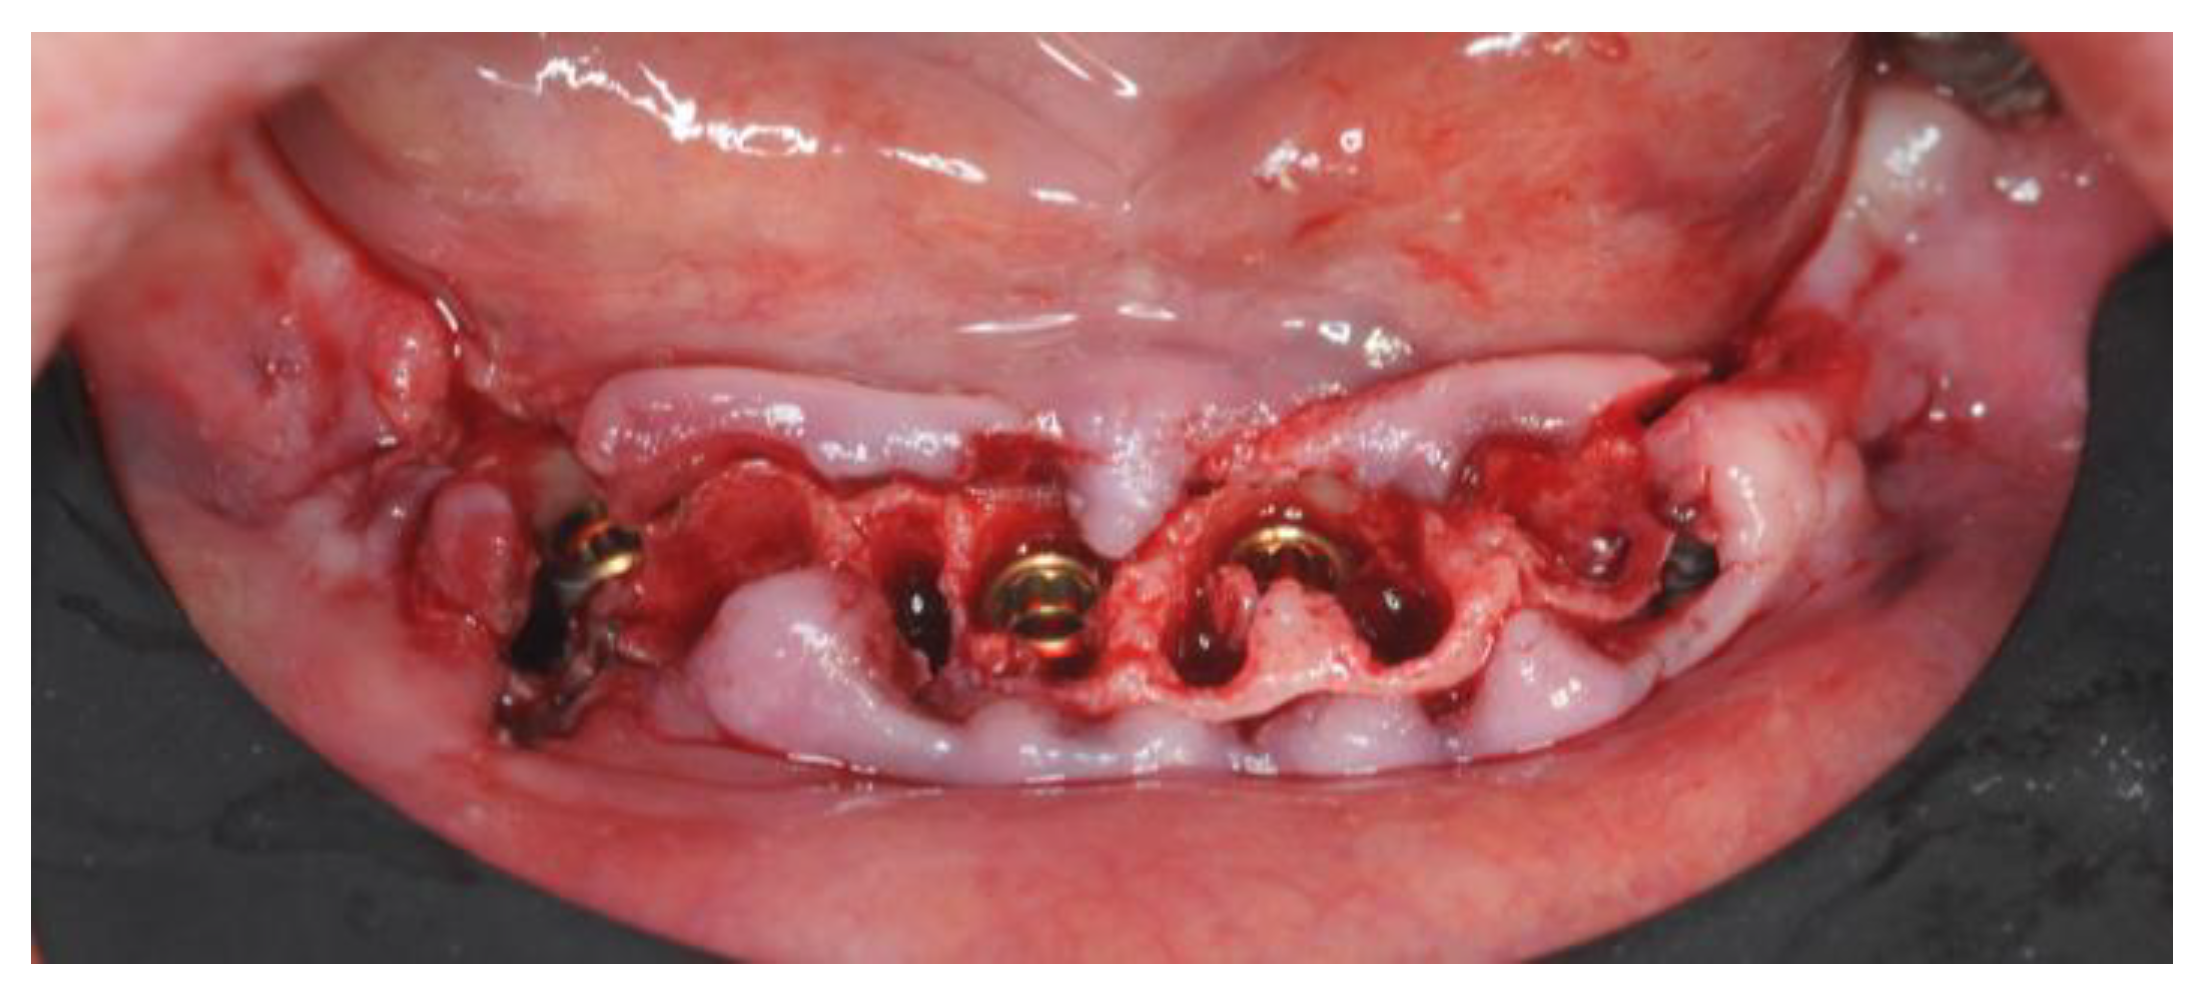

2.4. Surgery